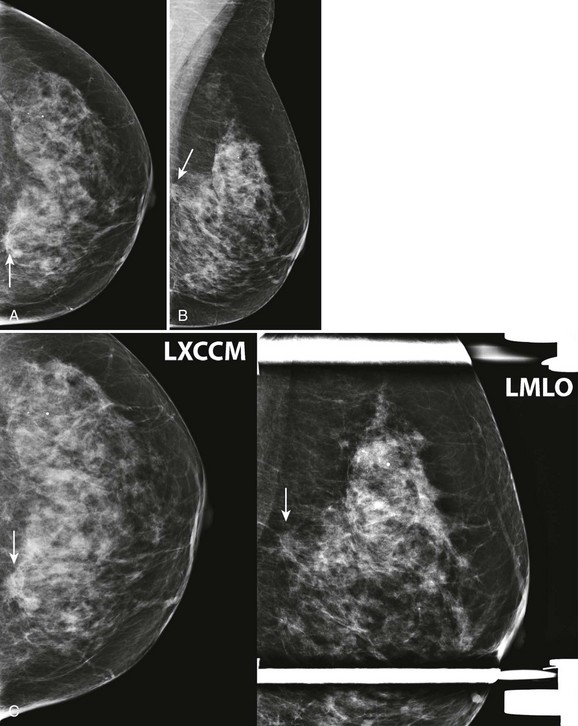

CASE 8-4. Screening mammogram of a 62-year-old woman. No previous mammograms are available. What are the significant findings? What management do you recommend? Can the rule of multiplicity be applied?

CASE 8-4. There are two masses in the left breast (upper inner quadrant and subareolar) and at least two much smaller masses in the anterior right breast (arrows; A and B). The rule of multiplicity cannot be applied because the 11 o’clock mass on the left has spiculated margins (circle).

These findings are better seen on spot compression views (arrows; C). US of the left breast reveals a mass with indistinct margins in the 11 o’clock position and a circumscribed mass in the subareolar region (D). US of the anterior right breast shows one hypoechoic solid mass with indistinct margins and one simple cyst (E).

Diagnoses: Left breast: 11 o’clock mass, IDC and DCIS; left subareolar mass, infiltrating carcinoma with mucinous features. Right breast: 11 o’clock mass, multifocal DCIS.